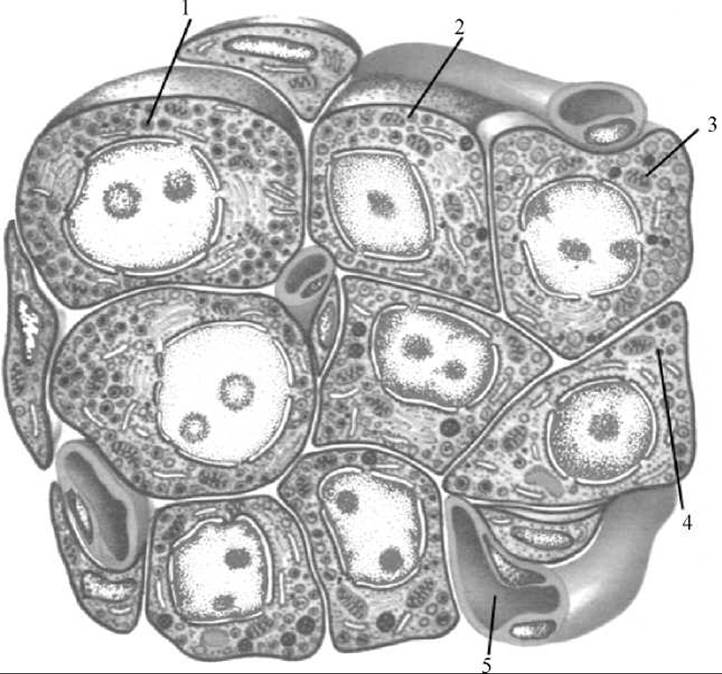

Мал. 229. Схема будови панкреатичного острівця

1 — альфа-Клітина; 2 — бета-клітина; 3 — дельта-клітина; 4 — РР-клітина; 5 — кровоносний капіляр

Панкреатичні острівці розвиваються із того ж епітеліального зачатка первинної кишки, що й Екзокринна частина підшлункової залози. Вони представляють собою овальної або округлої форми утвори величиною до 0,3 мм, деякі з них досягають 1 мм у діаметрі. Загальна кількість острівців коливається в межах 1—2 млн. Розміщуються острівці у всіх частинах підшлункової залози, але найбільше їх — у ділянці хвоста підшлункової залози. Вивідних проток вони не мають. Панкреатичні острівці сформовані зі скупчень епітеліальних клітин, оточених сполучною тканиною та великою кількістю капілярів, що проникають у їх середину. Панкреатичні острівці складаються з трьох типів клітин (альфа-, бета-, дельта-) (мал. 229). Переважають бета-клітини (60—80%), які виробляють гормон інсулін, що має багатосторонній вплив на Організм (головним є зниження вмісту цукру в крові). При цьому гормон сприяє перетворенню цукру в глікоген, стимулює утворення й відкладання жирів у підшкірній клітковині, а також підсилює Обмін вуглеводів у м’язах. Недостатнє виділення інсуліну призводить до виникнення хвороби — цукрового діабету. Ця хвороба характеризується підвищенням цукру в крові — гіперглікемією та появою цукру в сечі — глюкозурією. Альфа-клітини (складають 10—30%) виробляють гормон Глюкагон. Функціональна дія його протилежна інсуліну. Він стимулює розщеплення глікогену та жирів. Дельта-клітини (близько 10%) синтезують гормон соматостатін, який пригнічує вироблення гіпофізом гормона росту і знижує виділення інсуліну та глюкагону, а також ферментів підшлункового соку.